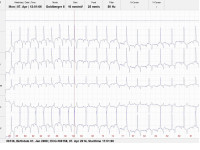

Vorhofflimmern bei einem Vollbluthengst

Vorhofflimmern bei einem 13 Jahre alten Vollbluthengst. Die Herzultraschalluntersuchung zeigte keine Klappeninsuffizienzen und alle Herzwerte lagen im Referenzbereich. Die Blutuntersuchung ergab keine Hinweise auf Elektrolytveränderungen oder Herzmuskelentzündung. Daher wurde die Diagnose primäres idiopathisches Vorhofflimmern gestellt, der Hengst wurde erfolgreich mit Chinidin entflimmert und kann heute wieder erfolgreich...